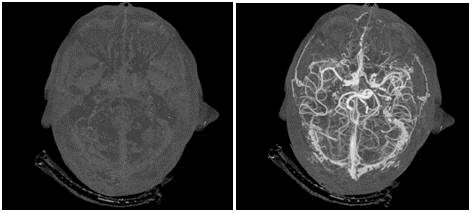

نخستین آزمایش بالینی نسل آینده اسکنر GE با قابلیت مشاهده اندام داخلی بدن مانند مغز، قلب، روده و عروق در بیمارستانی در جنوب فلوریدا انجام شد.

در این روش پرتوهای ایکس وارد بدن بیمار شده و رایانه، تصویر بسیار دقیقی از هر بخش تهیه میکند؛ بطورمثال امکان تهیه تصویر کامل از قلب در مدت تنها یک ضربان قلب فراهم میشود.

این روش توموگرافی رایانهای اشعه ایکس نیز نامیده میشود که اغلب در بیمارستان برای مشاهده تومورها، شکستگی استخوان و خونریزی داخلی استفاده میشود.

عروق، روده، قلب، مغز، استخوانها با جزئیات منحصربفردی به تصویر کشیده میشوند.